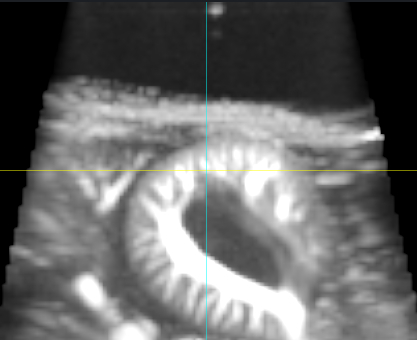

Abstract Body: Although endothelial dysfunction precedes cardiovascular diseases, non-invasive assessment of rodents' vascular function remains challenging. Ultrafast Doppler ultrasound has emerged as a powerful tool for assessing brain vascular function with high temporal and spatial resolution. However, its application to quantify in vivo hemodynamic changes in organs other than the brain has not been developed yet. Therefore, we propose to leverage the advanced 3D functional imaging capabilities of the Iconeus One system to measure real-time renal hemodynamic responses in a mouse model of hypertension. We hypothesized that hypertension impairs renal vascular reactivity, reflected by blunted Power Doppler values, an in vivo proxy for renal hemodynamic function. Seven-week-old male C57Bl/6 mice were administered retro-orbital injections of a hepatocyte-specific AAV2/8 virus encoding an HA-tagged Angiotensin II (AngII). Tail cuff blood pressure measurements (AAV: 147.5 mmHg vs. control: 132.5 mmHg, n=7, p<0.05), in addition to significant cardiac hypertrophy (p<0.05) confirmed the induction of hypertension. Mice were submitted to ultrasound measurement and Ultrasound Localization Microscopy (ULM) before and three weeks after AAV injection, and isolated renal and mesenteric arteries were analyzed ex vivo via wire myography. The 3D functional ultrasound (fUS) captured Power Doppler signals across sixteen transverse kidney planes. Signals were normalized to baseline to calculate Relative Doppler Values (RDVs), which were averaged across all planes to quantify renal hemodynamic activity. Mice underwent twelve-minute 3D fUS scans, administering bradykinin after two minutes. Results showed no difference in peak RDVs between baseline and post-injection control group. In contrast, hypertensive mice showed significant reduction in peak RDVs relative to pre-AAV baseline (n=7, p<0.05). Hypertensive mice showed significant decrease in peak RDVs following bradykinin injection compared to post-injection controls (p<0.05) and a marked decrease in endothelium-dependent relaxation to acetylcholine in renal and mesenteric arteries. ULM revealed a reduction in renal vascular density in hypertensive mice compared to controls. In conclusion, our findings demonstrate that ultrafast Doppler ultrasound is a promising, noninvasive tool for longitudinal in vivo assessment of renal endothelial function and correlates with ex vivo vascular reactivity measurements in renal and mesenteric arteries.